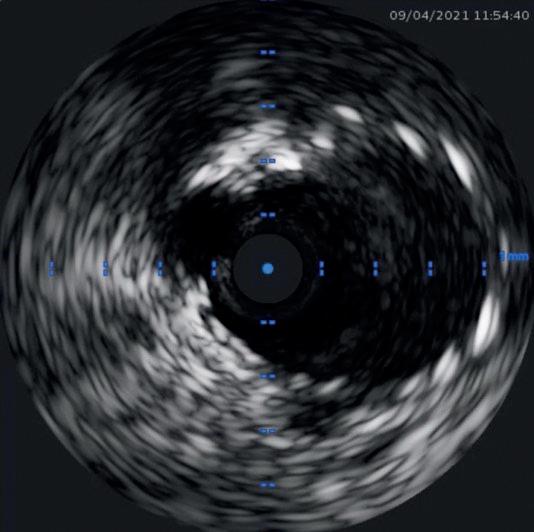

Intracoronary imaging

Among the major changes to the latest version of the guidelines is a new emphasis intravascular imaging. When performing revascularisation via PCI, intracoronary imaging—in the form of intravascular ultrasound (IVUS) or optical coherence tomography (OCT) —is deemed as being helpful to guide interventions and enhance results, especially in complex scenarios including left main disease, bifurcations, or long lesions.

on a multitude of randomised controlled trials showing consistent substantial clinical benefit,” said Lorenz Räber (Bern University Hospital, Bern, Switzerland), highlighting the importance of this new recommendation to Cardiovascular News. “Europe is lagging behind, as many believe angio is enough, so the upgrade is expected to fuel the use of imaging for complex lesions. Currently, there is no other technical refinement of PCI that reportedly improves clinical outcomes to the degree observed with intracoronary imaging.”

“Meta-analysis of randomised clinical trials had already shown that intracoronary image guidance of PCI improves patient outcomes and saves lives,” said Javier Escaned (Hospital Clinico San Carlos, Madrid, Spain). “But the IA recommendation for IVUS in the updated ESC guidelines is crucial, as it reflects expert consensus based on a definite body of evidence supporting the positive impact of IVUS, specifically for patients with anatomically complex lesions treated with PCI.”